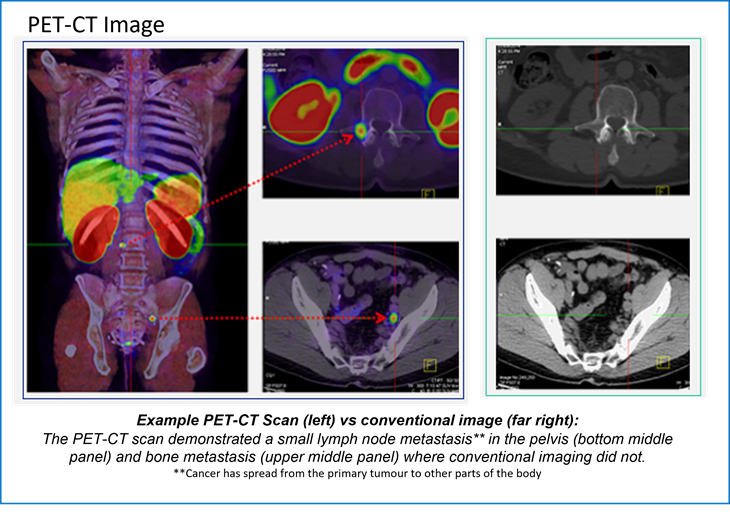

The PET-CT images ​

Positron emission tomography–computed tomography (PET-CT) is a global best practice diagnostic imaging tool that captures three-dimensional images of the body's biological functions. By utilising a small amount of a radiotracer (a radioactive substance that is used in medical imaging*), PET-CT scans can detect areas of abnormal metabolism or function in the body, including fast-growing cancers and infections.

PET-CT scans help doctors pinpoint the location of tumours or cancerous lesions, assess the extent of disease, determine whether lesions are benign or malignant, and identify any potential spread.

PET-CT provides oncologists with accurate information on the extent and severity of disease which enables them to better plan a patients cancer management and treatment, avoiding over or undertreatment, and potentially improving patient outcomes.